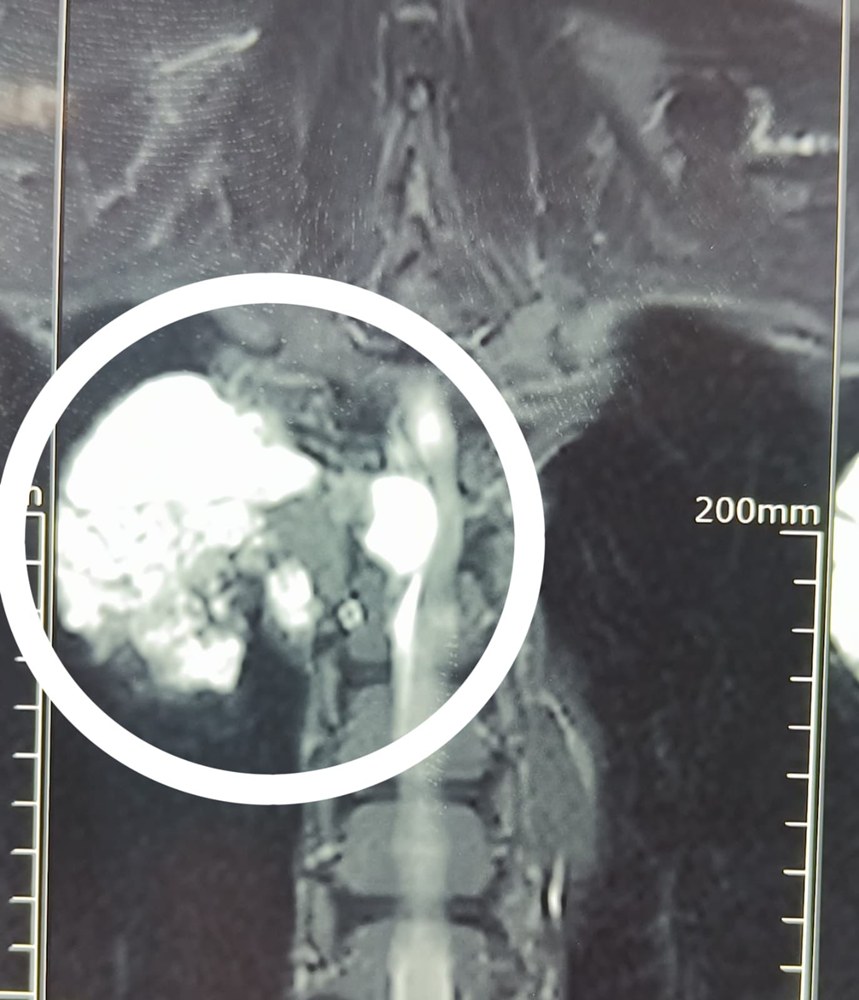

ग्रेटर नोएडा, 24 जुलाई 2025: फोर्टिस हॉस्पिटल ग्रेटर नोएडा की टीम ने एक ऐसा ऑपरेशन किया है, जो मेडिकल साइंस में बहुत कम देखने को मिलता है। ग्रेटर नोएडा निवासी 44 वर्षीय सुबोध कुमार की रीढ़ की हड्डी में मायक्सॉइड मूल का एक अत्यंत दुर्लभ और बड़ा ट्यूमर पाया गया, जो पीठ के ऊपरी हिस्से से लेकर सीने तक फैला हुआ था। भारत में इस तरह के मामलों की संख्या बेहद कम रही है।

ट्यूमर का आकार एक क्रिकेट बॉल जितना था और वह रीढ़ से होते हुए छाती के अंदर मीडियास्टाइनम क्षेत्र तक फैल चुका था। इसे हटाना एक अत्यंत संवेदनशील और चुनौतीपूर्ण कार्य था, क्योंकि यह स्पाइनल कॉर्ड से चिपका हुआ था।

ऑपरेशन का नेतृत्व डॉ. हिमांशु त्यागी (निदेशक एवं प्रमुख, ऑर्थोपेडिक्स और स्पाइन सर्जरी) ने किया। उनके साथ डॉ. राजेश मिश्रा और डॉ. मोहित शर्मा की टीम भी इस जटिल सर्जरी में शामिल रही। यह ऑपरेशन करीब चार घंटे तक चला, जिसमें माइक्रोस्कोपिक सर्जरी, इंट्रा-ऑपरेटिव न्यूरोमॉनिटरिंग और इमेज गाइडेंस जैसी अत्याधुनिक तकनीकों का उपयोग किया गया।